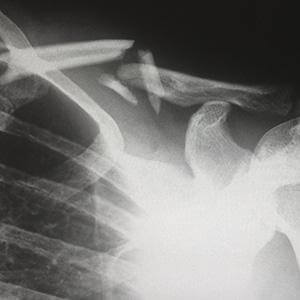

El curso repasa el sistema musculoesquelético del cuerpo humano y las fracturas y traumatismos más habituales. Dedica un capítulo a la alimentación y el deporte.Programa

- Fracturas.

- Estudio radiológico de las fracturas – tipos, manifestaciones, complicaciones.